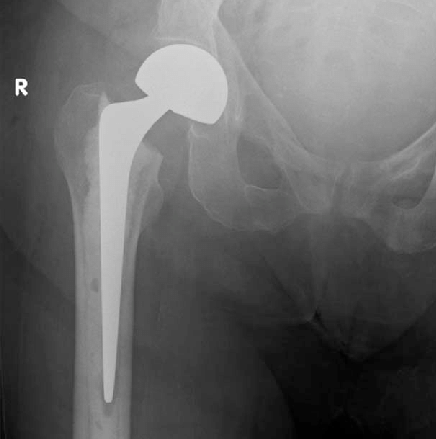

A Cemented Half Hip Replacement (Hemiarthroplasty) is a surgical procedure where the damaged head of the thigh bone (femur) is replaced with an artificial implant. Unlike total hip replacement, only half the joint is replaced, and the new femoral head is fixed using bone cement for immediate stability.

- A specially designed metal implant is inserted into the femur

- Bone cement is used to secure the implant in place